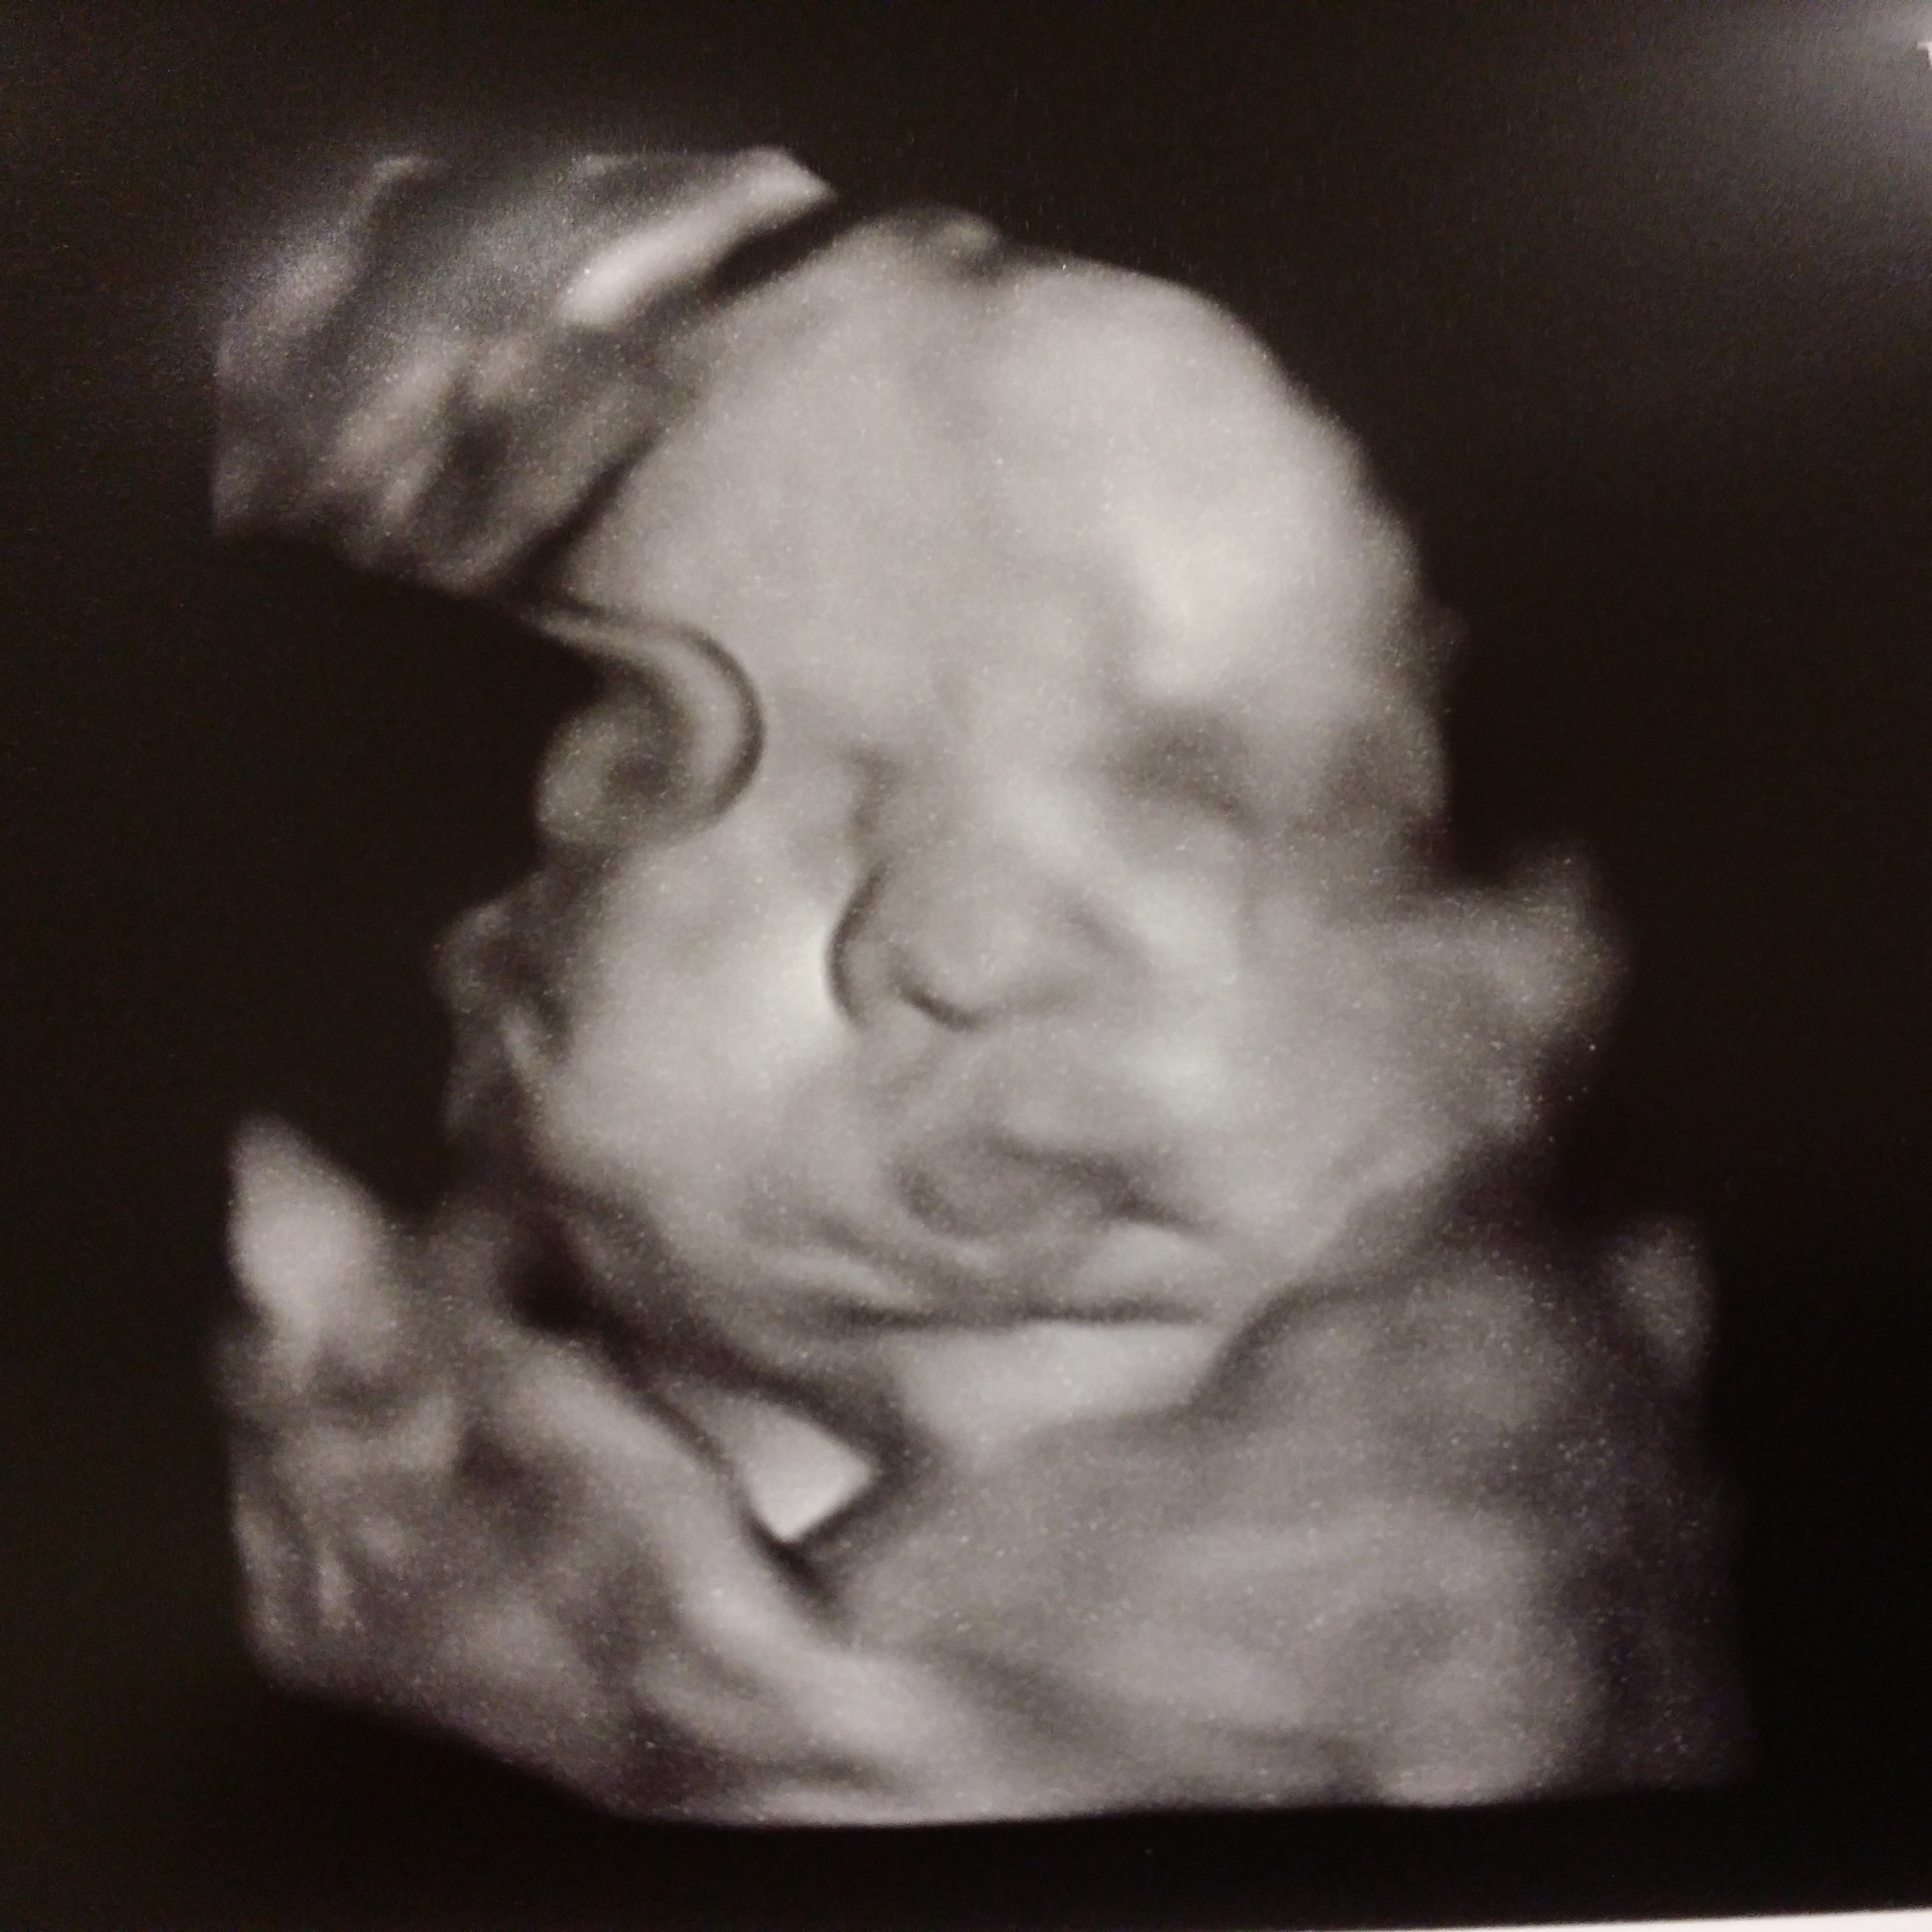

And a little AW of our little man sticking out his tongue.